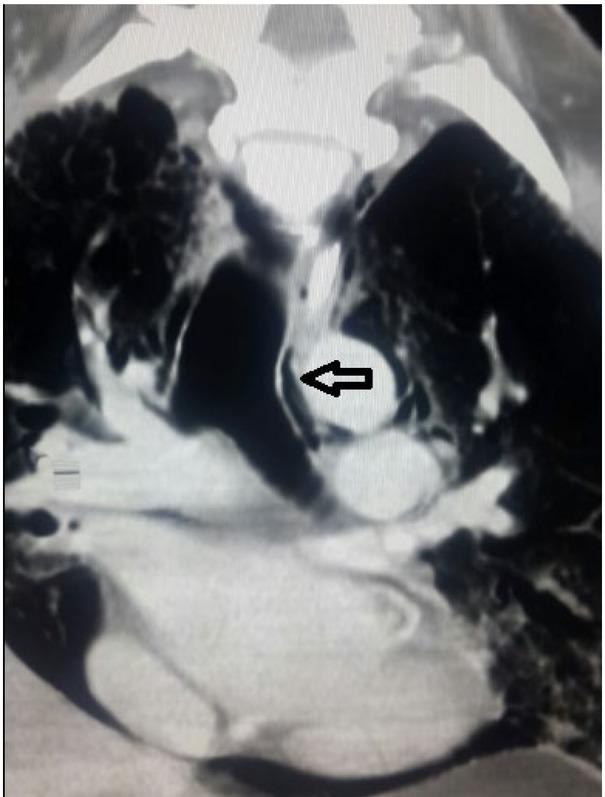

Fig. 1C